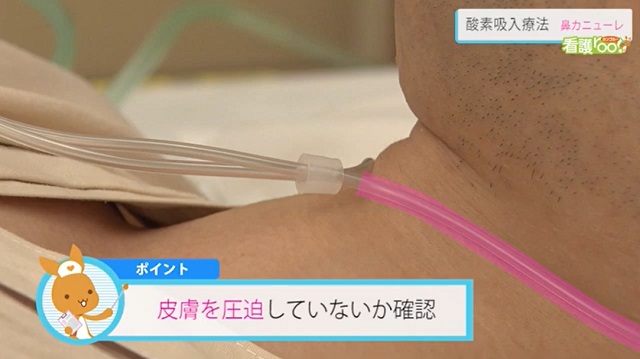

酸素ボンベによる酸素投与動画でわかる看護技術看護roo! カンゴルー。

酸素流量計の準備~カニューレの装着動画でわかる看護技術看護roo! カンゴルー。

酸素流量計の準備~カニューレの装着動画でわかる看護技術看護roo! カンゴルー。

酸素流量計の準備~カニューレの装着動画でわかる看護技術看護roo! カンゴルー。